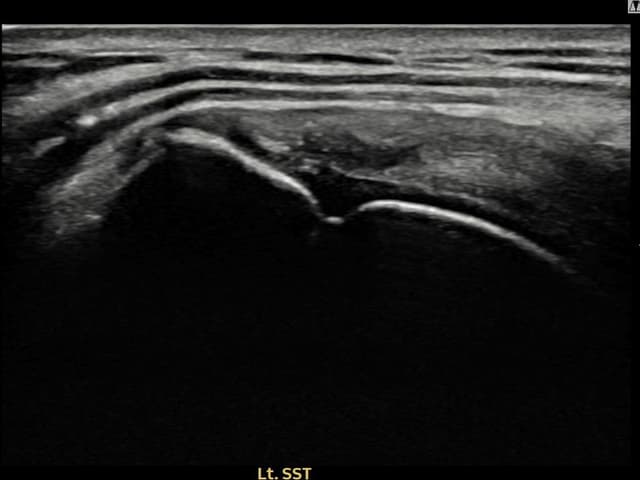

[촬영시기:24.01.08~24.03.14]

[어깨인대 축소봉합술] 좌측 어깨 통증으로 팔을 올리기 불편하여 내원하셨습니다.